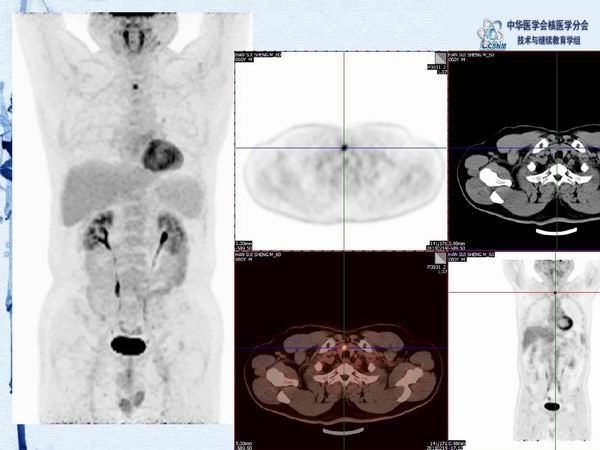

讲座40:PET/CT图像判读和报告规范-姚稚明